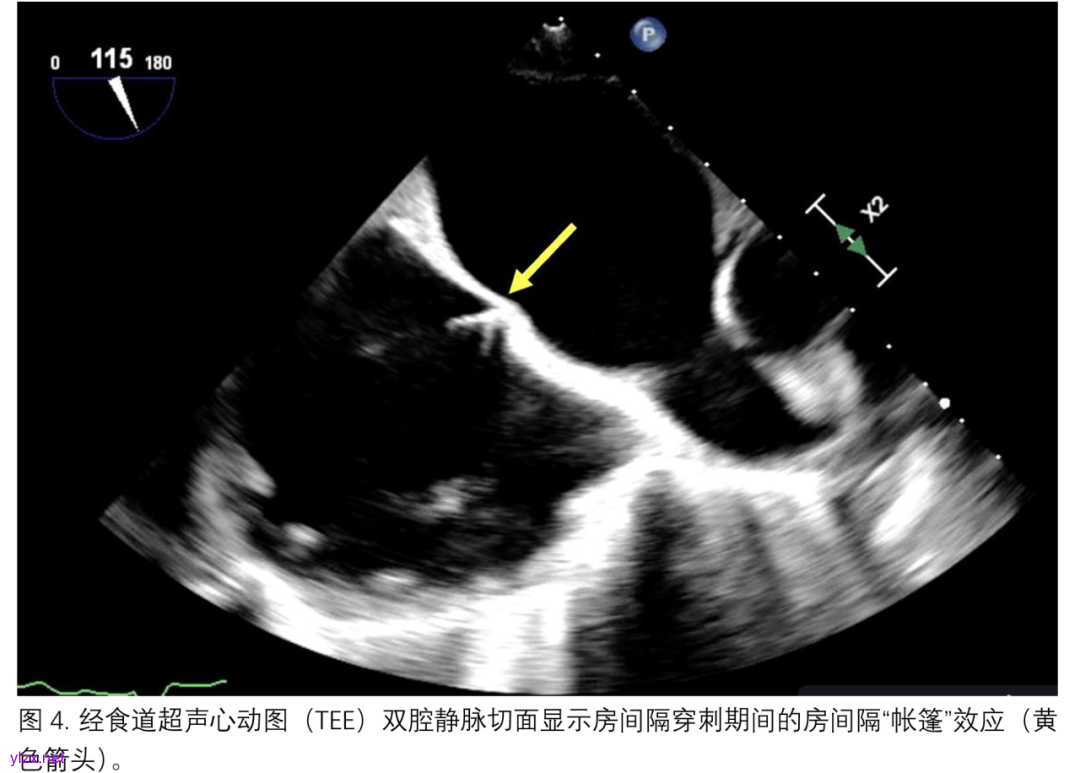

如果左心室减负不足,则需要放置左心室引流管(LV vent),并且与更高的ECMO撤机概率和降低死亡率相关。超声心动图可以作为放置和管理左心室引流管的有用指导工具,无论采用何种左心室引流策略。左心室引流管可以在经食道超声心动图(TEE)引导下直接放置在左心室心尖或左心房(通过肺静脉)。此外,左心室减负也可以通过房间隔造口术实现。房间隔造口术通常在TEE引导下进行,TEE有助于观察房间隔的“帐篷”效应,并且可以从正面提供三维图像引导,帮助介入医生进行精细的心内操作,避免心脏或血管损伤(图4)。主动脉内球囊反搏(IABP)是另一种常用于通过降低全身后负荷来解决左心室扩张的策略。当与ECMO联合使用时,IABP可以改善股动脉血流速度,并与单独使用ECMO相比提高总生存率。TEE引导已被用于指导IABP的适当放置。IABP导丝应被观察到位于左锁骨下动脉开口下方1-2厘米处,且应通过观察确认没有新的心脏损伤、主动脉夹层或与粥样硬化疾病发生干扰。最后,LV Impella(Abiomed)是一种小型化的左心室辅助装置,它提供从左心室到升主动脉的持续引流血流。它常与ECMO治疗联合使用,以提供左心室减负以及ECMO撤机后的过渡性机械循环支持,并且与单独使用ECMO相比,联合使用时与更高的生存率相关。TEE常用于指导Impella的放置,并应在主动脉瓣的室侧显示Impella尖端距离主动脉瓣环3.5-5.5厘米(具体取决于Impella型号),同时确认没有发生主动脉夹层、心包填塞或新的主动脉瓣或二尖瓣功能障碍,或卵圆孔未闭(图5)。